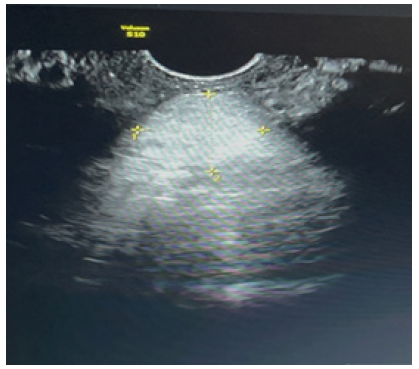

A.S, a 45-year-old woman, has a history of two vaginal deliveries and a Transobturator Tape (TOT) procedure performed 10 years ago for urinary incontinence; she has no other illnesses, allergies, or history of medication use; her body mass index is 27, and she smokes 1.5 packs of cigarettes per day. The patient underwent TLH (Total Laparoscopic Hysterectomy) and Bilateral Salpingectomy due to abnormal uterine bleeding, with preoperative pathology tests revealing benign results. During the operation, the vaginal cuff was circumferentially cut from front to back using a monopolar hook, and the vaginal cuff was sutured with 2.0 V-loc. Postoperative follow-ups were uneventful. 1.5 months after the operation, she presented to the gynecology clinic with complaints of bloody vaginal discharge, a sensation of pressure towards the vagina, and lower abdominal pain following coitus. On speculum examination, a 3x3 cm prolapsed mass from the vaginal cuff and minimal vaginal bleeding was observed (Figure 1). Vital signs were stable, together with an unremarkable abdominal examination. Her bowel sounds were also found to be normoactive on auscultation. Vaginal ultrasonography showed a solid mass above the cuff, with no evidence of bowel prolapse (Figure 2). Laboratory tests, including hemogram and biochemical studies, were normal. The patient was thus admitted to emergency surgery for transvaginal cuff repair due to suspicion of vaginal cuff dehiscence and omental prolapse. Peroperatively, the omentum was reduced back into the abdomen via vajinal route in trandelenberg position (Figure 3). Upon further examination the vaginal cuff was found to be partially necrotic. Single interrupted sutures with 0 Vicryl were placed in a 4cm long dehisced cuff (Figure 4). No issues were detected during the 1st week and 2nd-month postoperative follow-up.